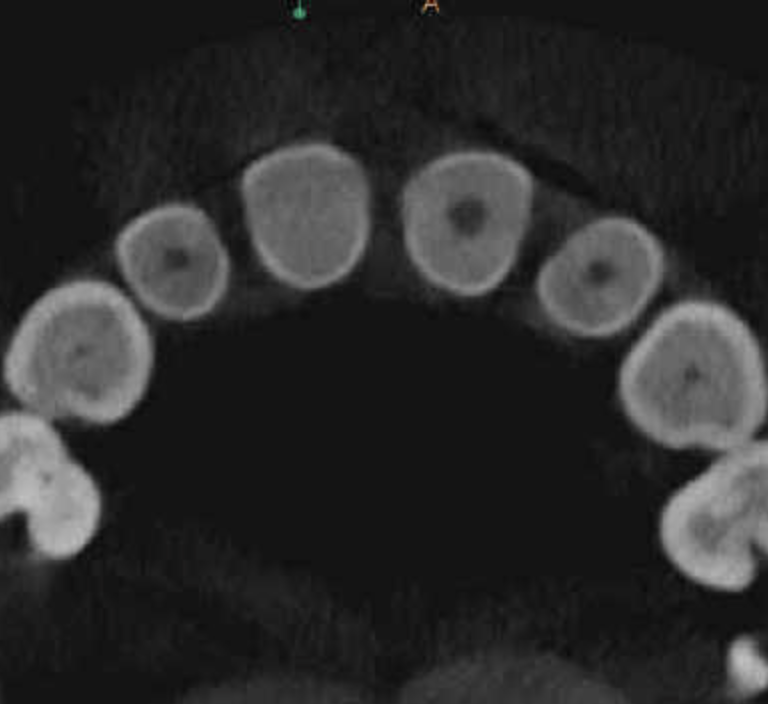

Casos de anatomia compleja

Bifurcación conducto palatino apical